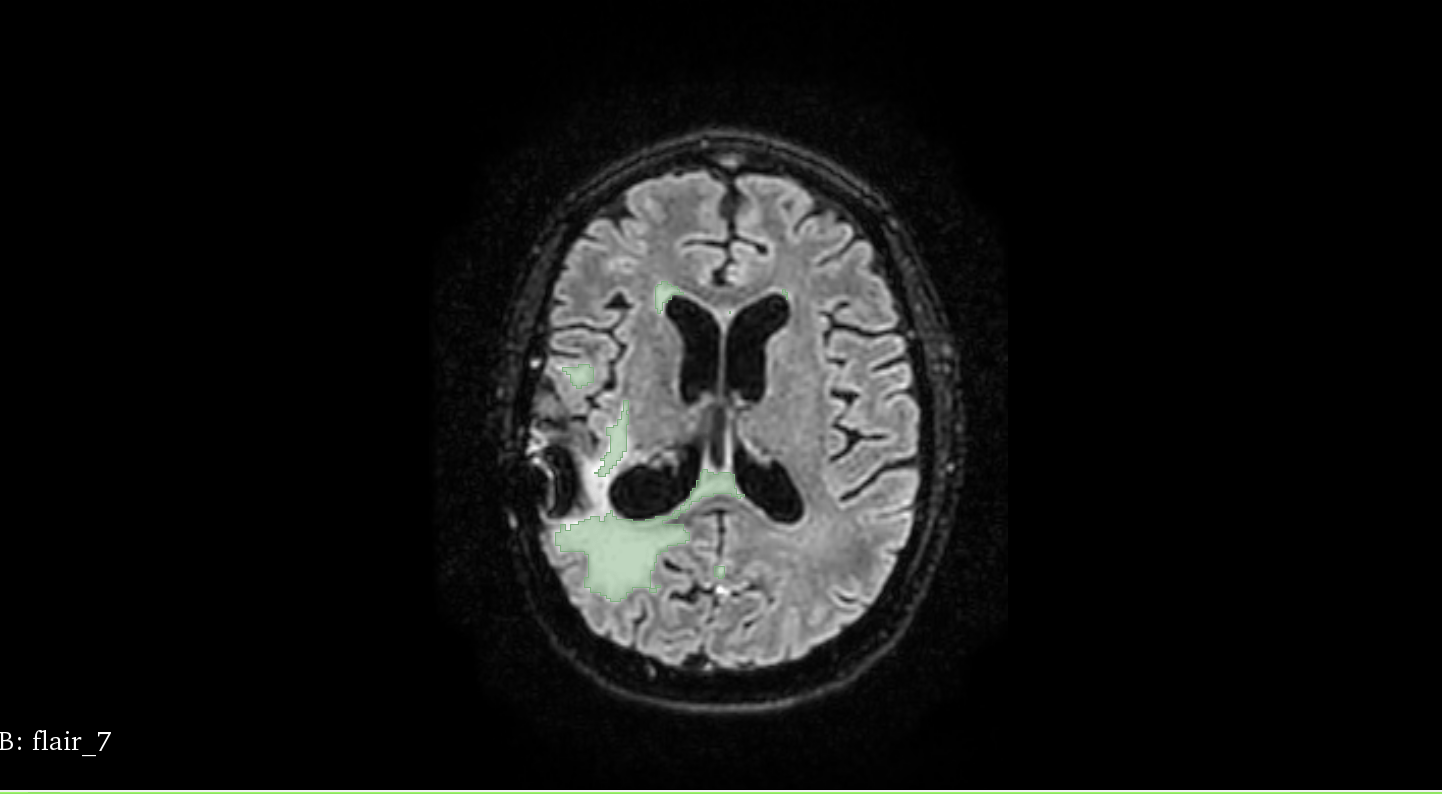

• Image FLAIR - Avec le crane

• prob - probabilité / carte (presque) entre 0 et 1 à l'emplacement des WMH

• segm - segmentation

Patient 58